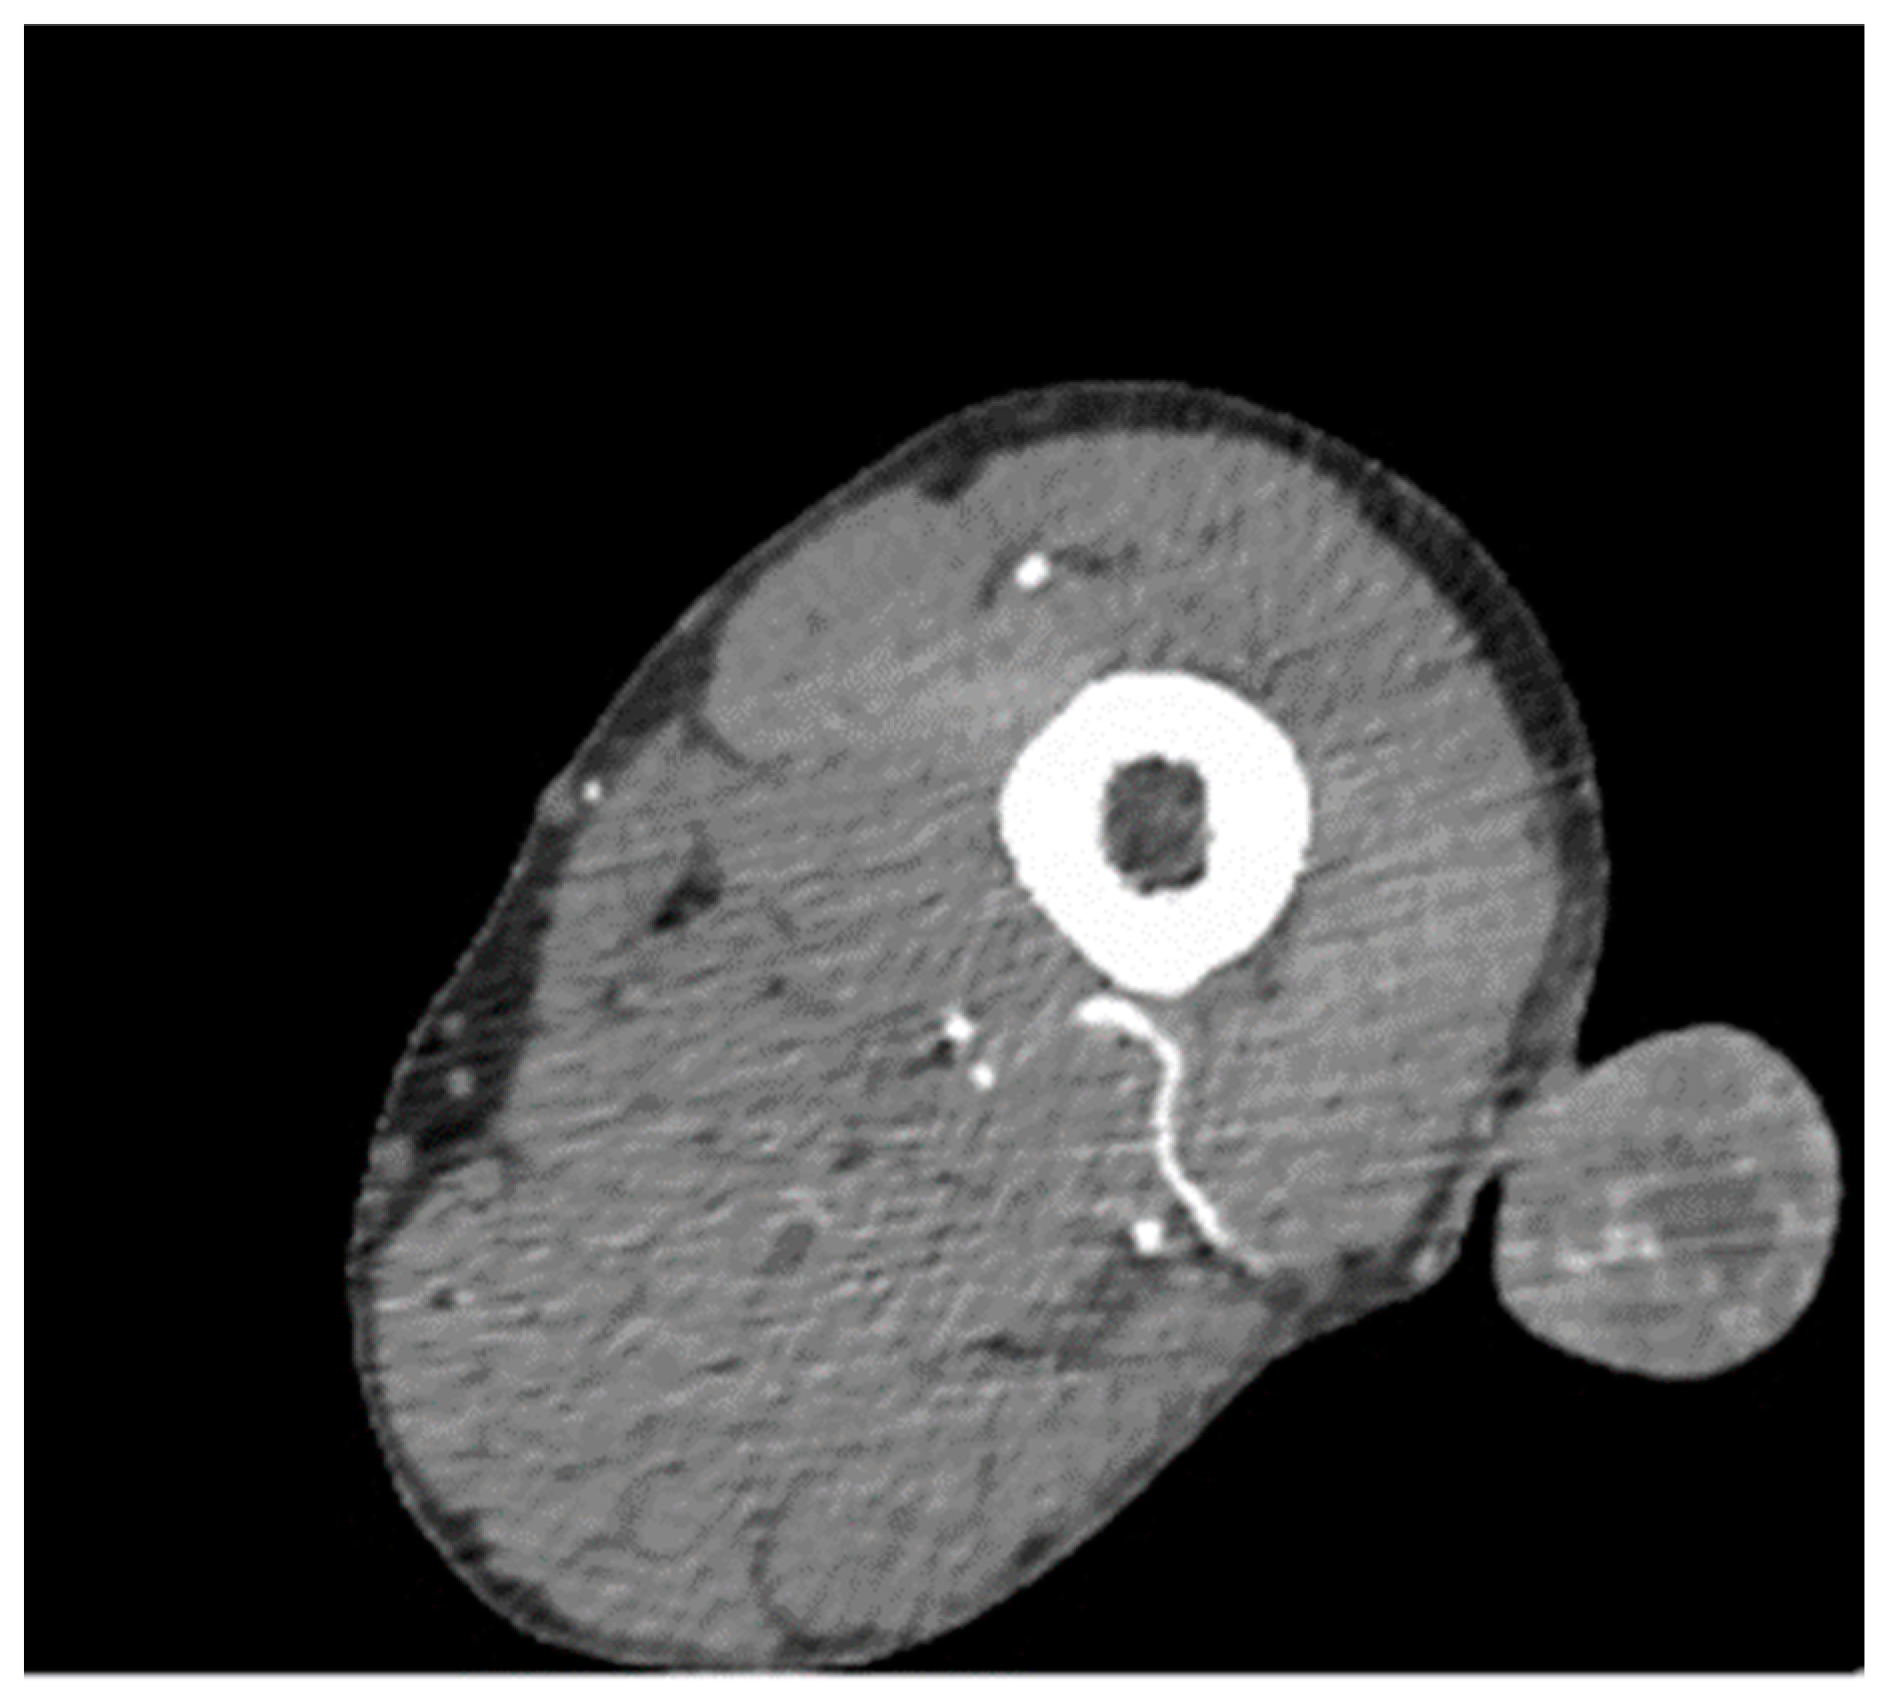

Glomangioma Supply from Profunda Femoris Artery in Peripheral Artery Disease

3. Results